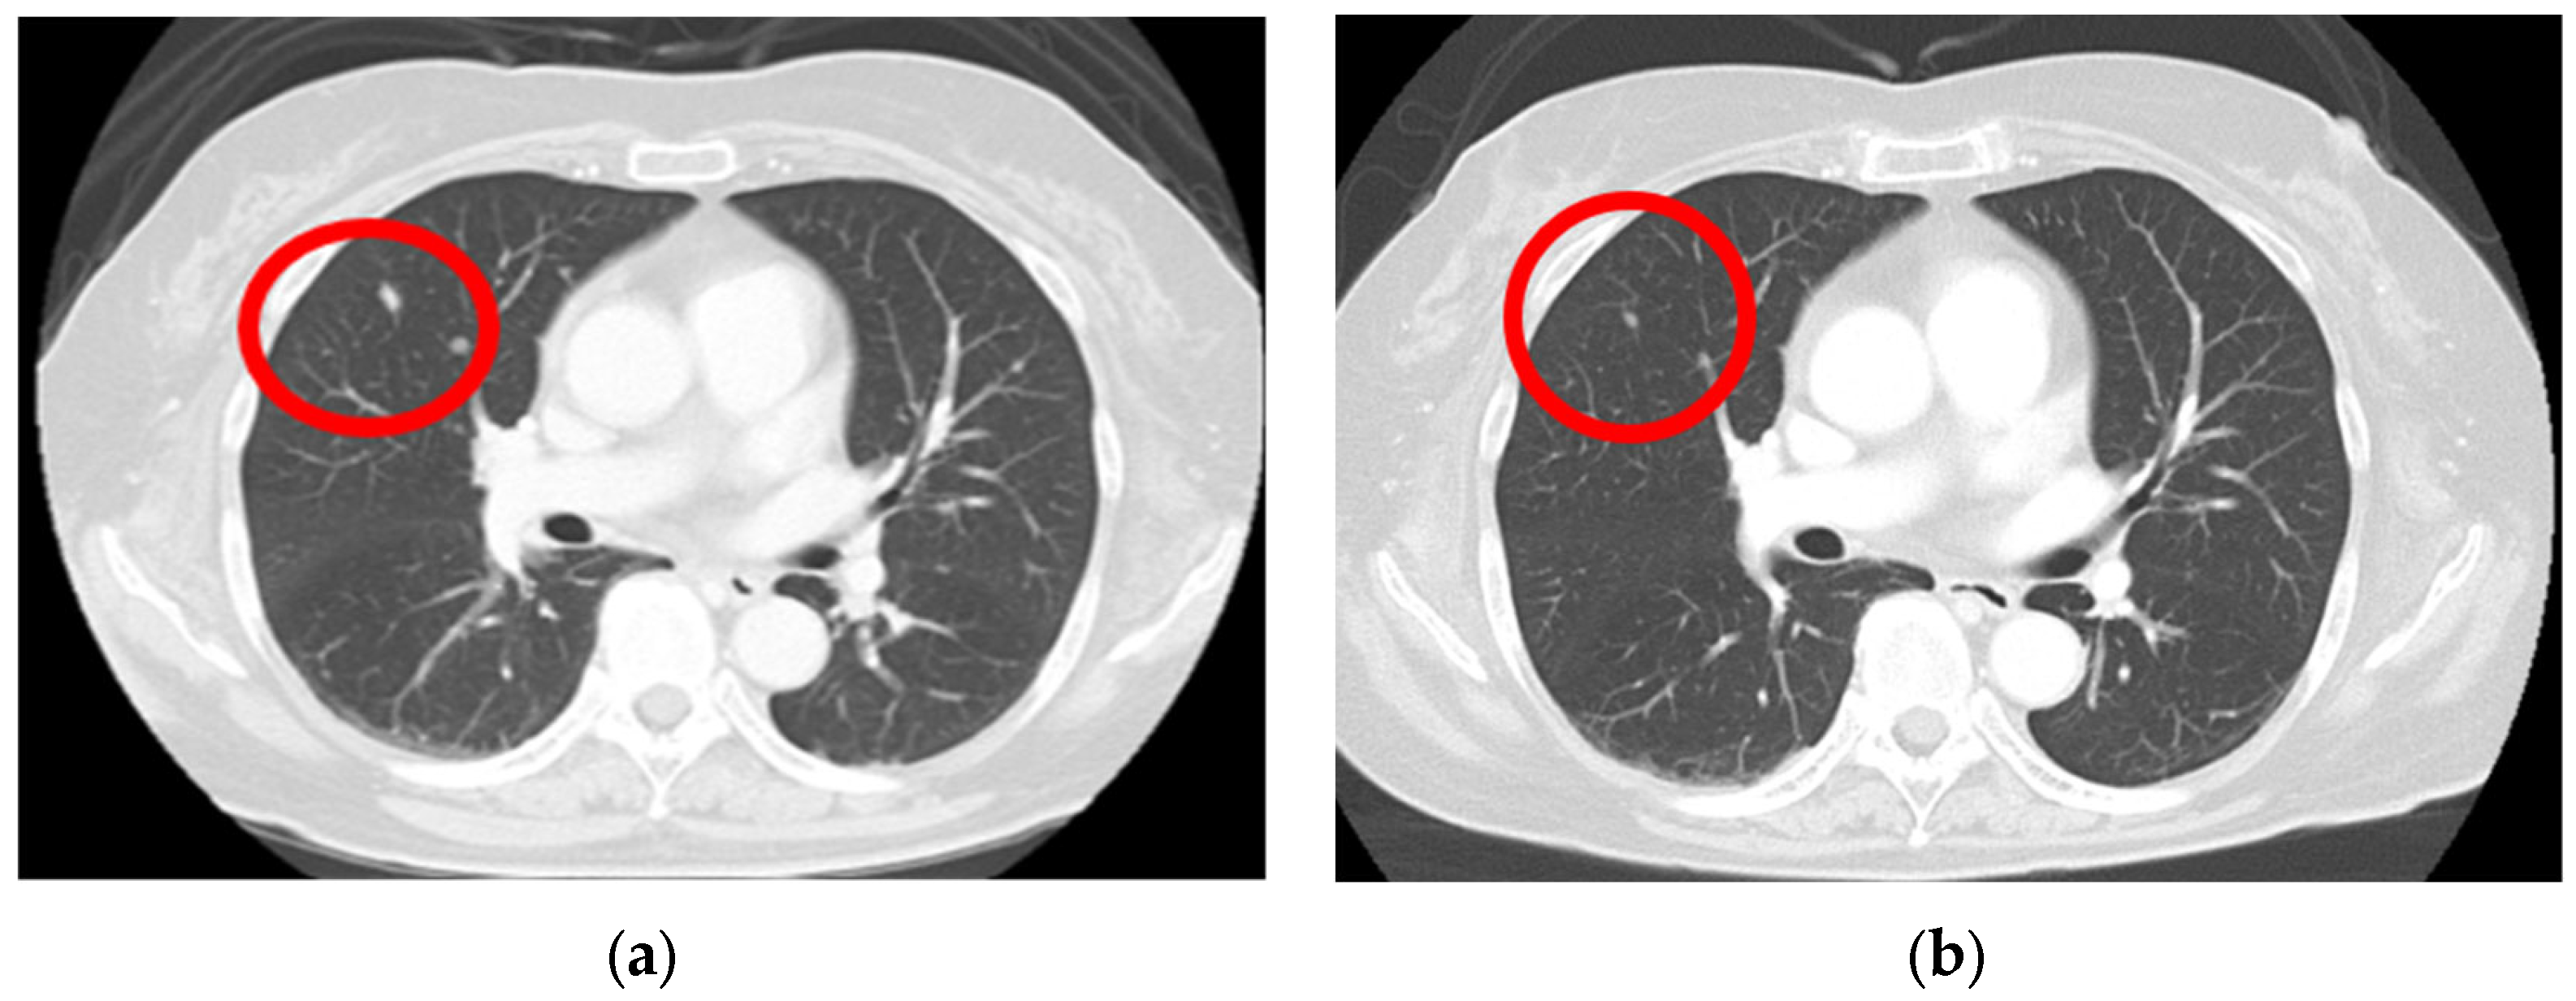

2. Case Presentation